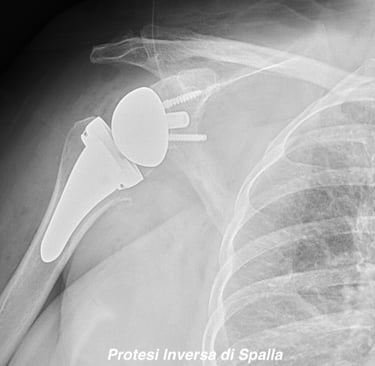

Chirurgia di Spalla e Gomito

Eseguo visite specialistiche, trattamenti conservativi e interventi specialistici sulla spalla e sul gomito, sia artroscopici sia a cielo aperto, per il trattamento delle principali patologie ortopediche e traumatiche di queste articolazioni.

Artrosi di spalla (Gleno-Omerale)